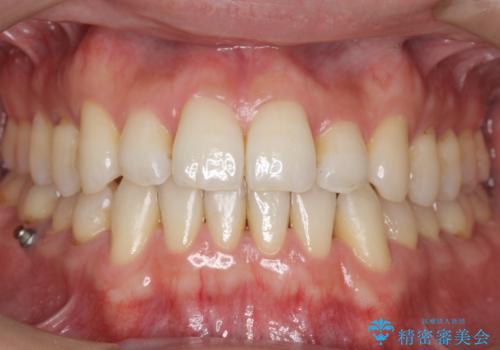

ワイヤーによる全体的ながたつきの矯正治療